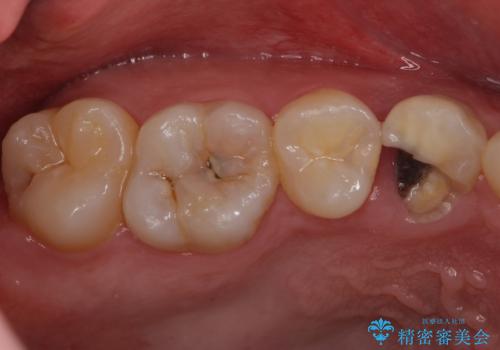

- 上の歯が大きく欠けたとのことで来院されました。

検査の結果、虫歯が大きくなりすぎたせいで薄くなった歯が欠けてしまった経緯が考えられました。

レントゲン画像上で歯茎の深いところまで虫歯になっており、保険治療では抜歯適応になってしまいます。